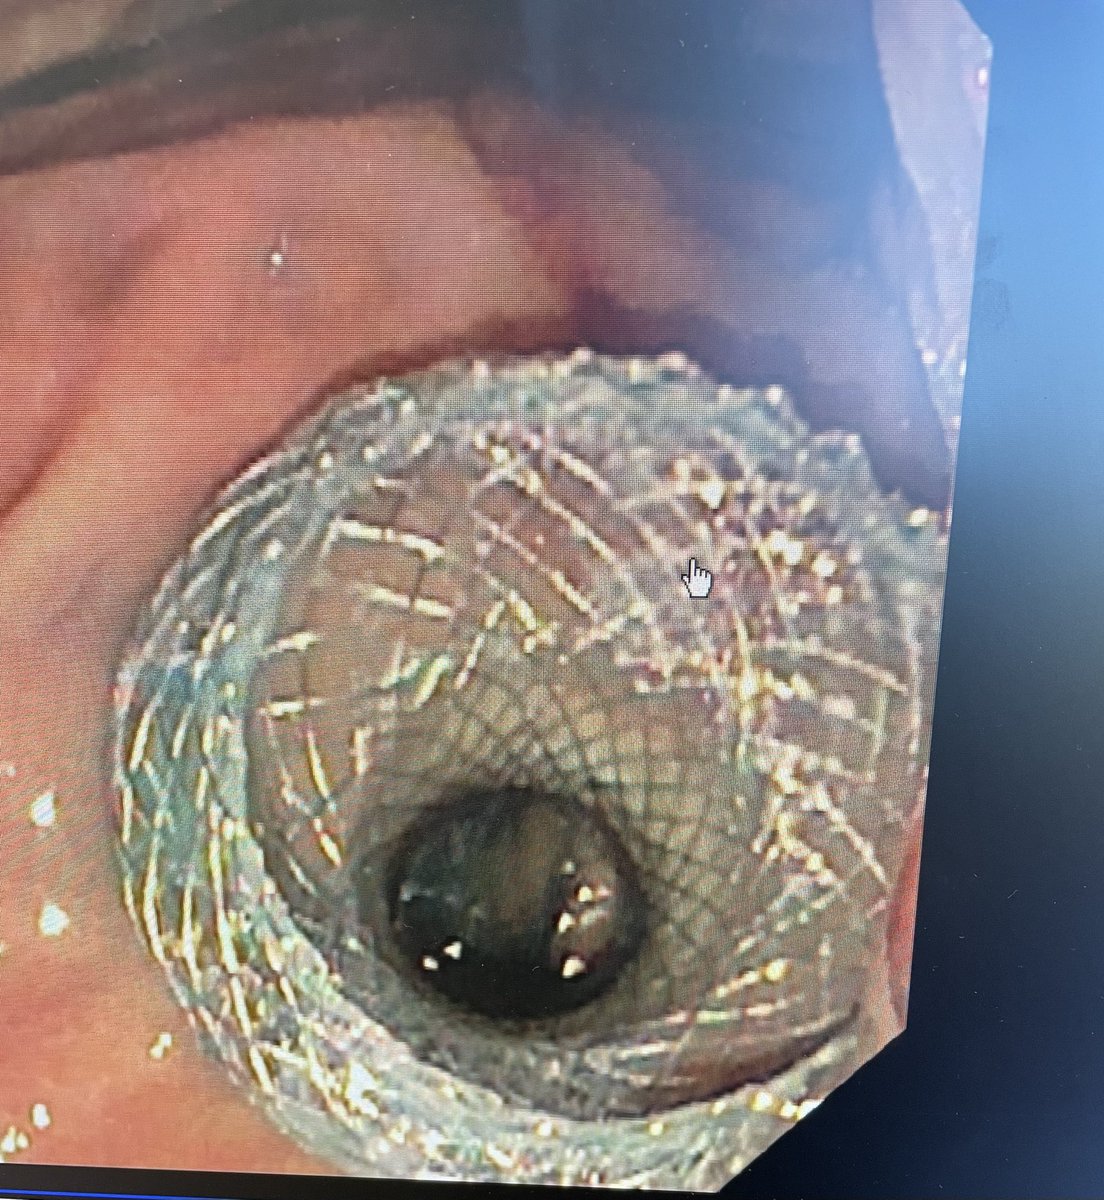

@Bashar_Qumseya Cholangitis with cbd wall thickening ? Stone impacted or papillary stenosis